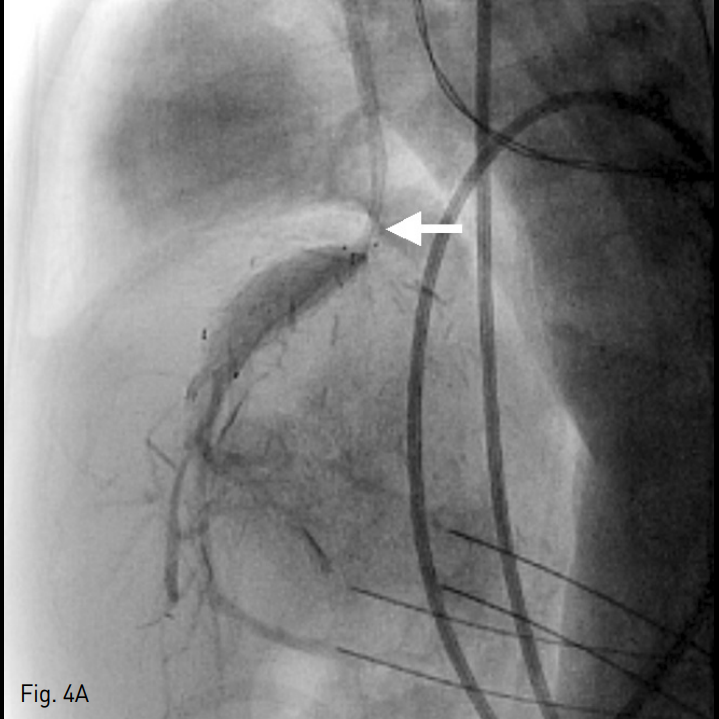

시술 후 환자의 컨디션과 혈액 검사 소견 호전되어 퇴원하였으나 시술 2주 후 다시 복부 팽만과 식이 섭취감소를 호소하며 내원하였다. 혈액 검사 소견 상 혈소판 수치 혈소판 수치 106,000/mm3, INR 1.82, albumin 3.4g/dL, total bilirubin 1.1mg/dL, AST 48U/L, ALT 49U/L로 첫 시술 전 보다는 정도가 낮으나 악화되어 있었다. 전산화 단층 촬영 상 간실질의 울혈을 시사하는 간실질의 불균질한 조영 증강이 관찰되었으며, 스텐트 내 충만결손 병변은 관찰되지 않았다(Fig. 3). 다시 환자의 내경정맥을 통해 5 Fr 혈관조영술용 카테터를 삽입하여 간정맥 내로 진입하였으며, 조영제 주입 시 혈류 정체와 함께 스텐트의 끝 주변으로 협착이 관찰되었으며 압력 차이는 19mmHg로 측정되었다 (Fig. 4A). 간정맥 협착 해소를 위해 14mm x 30mm 자가확장형 스텐트 (Zilver)를 삽입하고 8mm x 40mm 풍선 카테터 (Mustang)을 이용하여 혈관성형술을 시행하였다. 이후 시행한 간정맥 조영술 상 우심방으로의 혈류가 회복되었으며 압력 차이가 3mmHg로 줄어들었다 (Fig. 4B).

Fig. 4

A. On contrast injection after catheter access to the hepatic vein via transjugular route, there was persistent stenosis at the anastomosis site (arrow) which is not covered by the previously inserted stent.

B. After additional stent inser tion (14mm x 30mm) and balloon angioplas ty (8mm x 40mm) at the anastomosis site the flow via the newly inserted stent (arrowheads: stent markers) to the right atrium restored, and the pressure gradient dropped from 19mmHg to 3mmHg.